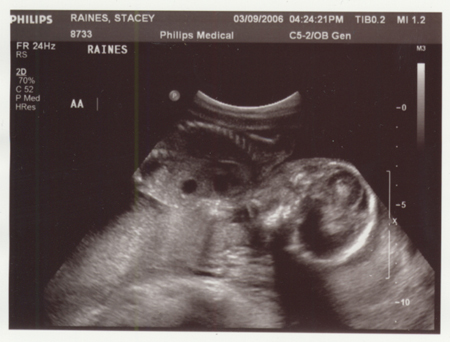

So have you figured out the answer. Excited or shocked? Well we are to.. very excited. So now we guess, this is the time to shock you. If you look close, these are not two pictures of the same.

Yep, TWINS!! And if you think trying to tell the difference above now is difficult, just wait until July/August when you can hold them.